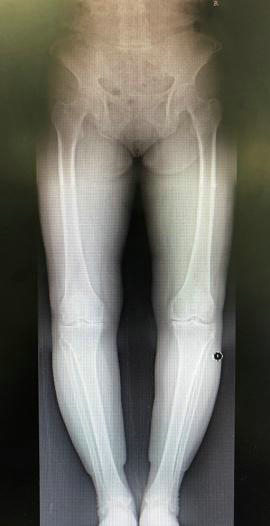

影像学检查有助于明确膝关节骨性关节炎的进展程度。X线平片检查早期可无明显异常,逐渐出现关节间隙狭窄,表明关节软骨开始变薄。开始时关节间隙在不负重时正常,承重后出现狭窄。病变后期,关节间隙有显著狭窄,而后出现骨质硬化,最后关节边缘变尖,有骨赘形成。CT及MRI检查可早期发现关节软骨及软骨下骨质的异常改变。

值得一提的是,并不是所有人的影像学检查结果都与临床症状完全符合,由于患者的耐受程度不同,有一些影像学检查表现很轻微的患者,临床症状也可能很重,而对于运动强度较大的特殊人群,如专业运动员等,即使影像学检查显示关节退变严重,也可以没有明显临床症状。

膝人工关节置换术前术后X线片